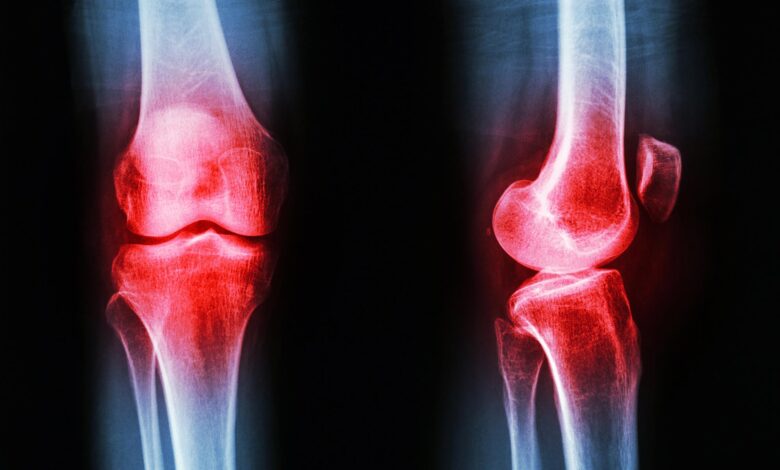

Артрит коленного сустава — это воспалительное заболевание, которое может привести к серьезным последствиям, если не обнаружено и не лечится вовремя. Одним из ключевых аспектов успешного лечения является своевременное распознавание симптомов артрита коленного сустава.

Основные симптомы артрита коленного сустава включают:

- Боль и отечность в колене;

- Сильная жжение и покраснение в районе сустава;

- Ограничение подвижности колена;

- Хруст и скрип при движении;

- Отек и утолщение сустава.